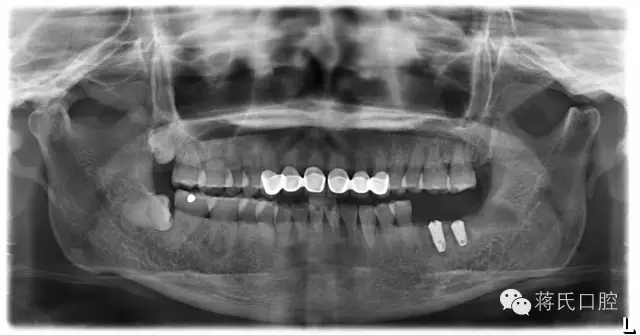

2.种植后全景片